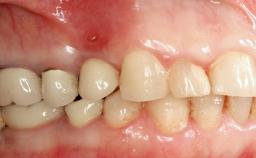

Oral implants are highly successful and offer long-term benefits, especially in the rehabilitation of edentulous patients or patients with oral defects following ablative tumor surgery (Albrektsson and coworkers 1986), and also after radiation therapy (Schiegnitz and coworkers 2014). With the number of implants placed globally going into the millions, implant dentists have observed some rare adverse events. Although carcinogenesis around implants is an exceedingly rare phenomenon, we recently reported about 15 patients treated for carcinomas adjacent to implants at our clinical department over a period of fifteen years (Moergel and coworkers 2014). The following case represents a patient of this cohort; it discusses possible risk factors and makes suggestions for a recall schedule. A 70-year-old woman was referred to our outpatient department for evaluation of a rapidly growing macroscopic alteration of the mucosa in the left mandible.

Prosthesis Type FDP